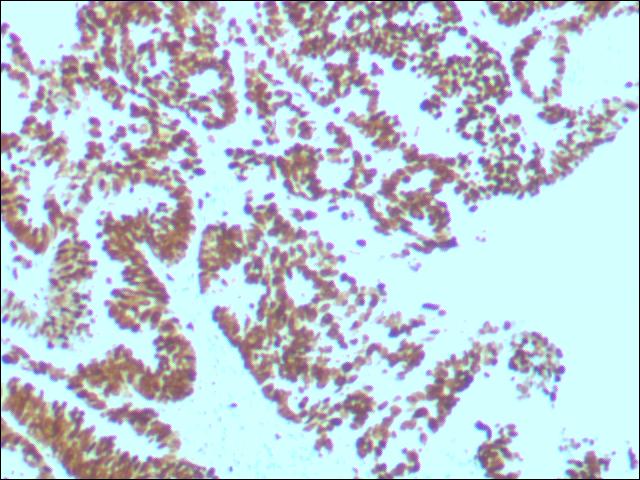

免疫组织化学病理诊断

免疫组化,是应用免疫学基本原理——抗原抗体反应,即抗原与抗体特异性结合的原理,通过化学反应使标记抗体的显色剂显色来确定组织细胞内抗原对其进行定位、定性及相对定量的研究。